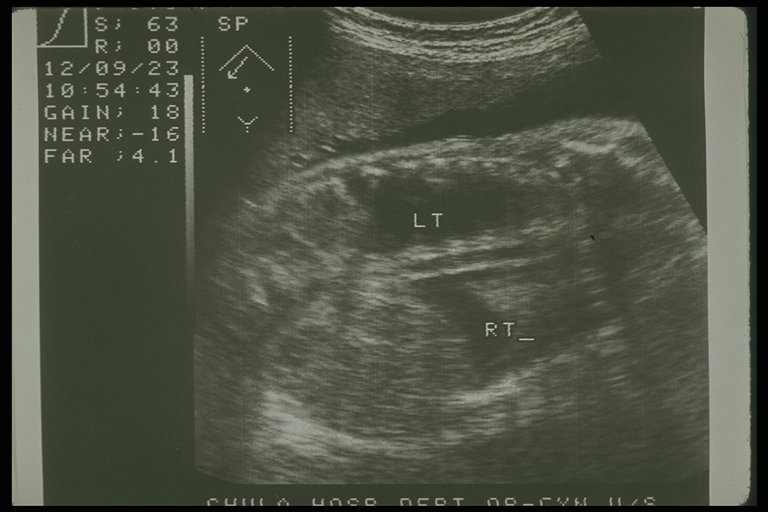

Prenatal ultrasonography showed bilateral congenital chylothorax, massive pleural effusion was detected in both chest cavity